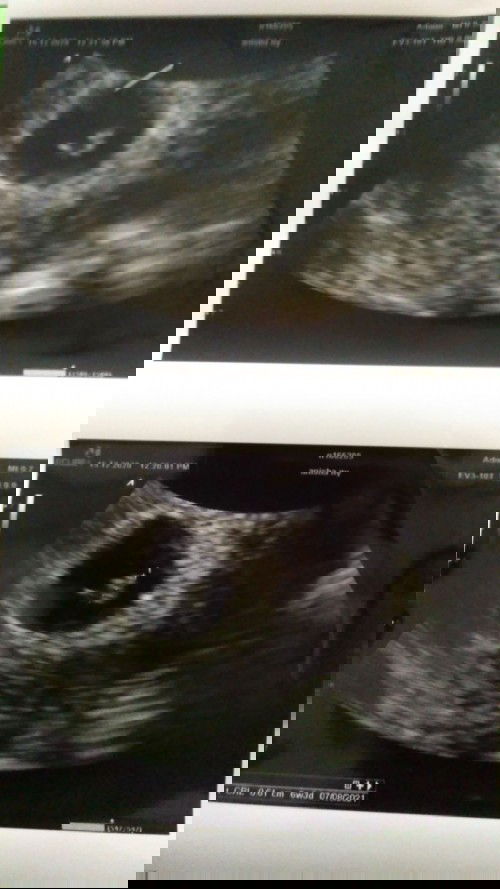

Usg yg tepat untuk 3 bulan usg yg apa ya?

Bun mau tanya usg untuk 3 buln yg baiknya yg apa ya?transvaginal,2d atau 4d ya?akhir buln mei sudah usg transvaginal sudah terdengar detak jantung.kalo buat yg usia 3 buln bagusan usg yg apa ya?🙏